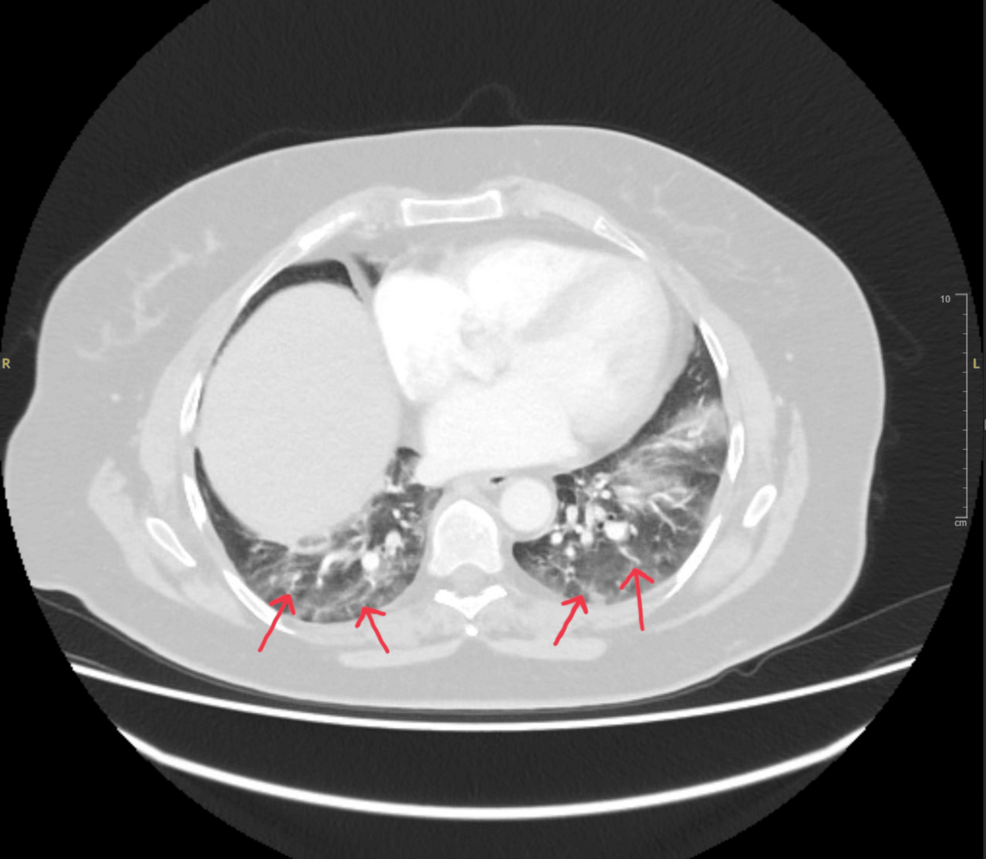

Embolie pulmonaire retardée: traumatisme et diagnostic manqué